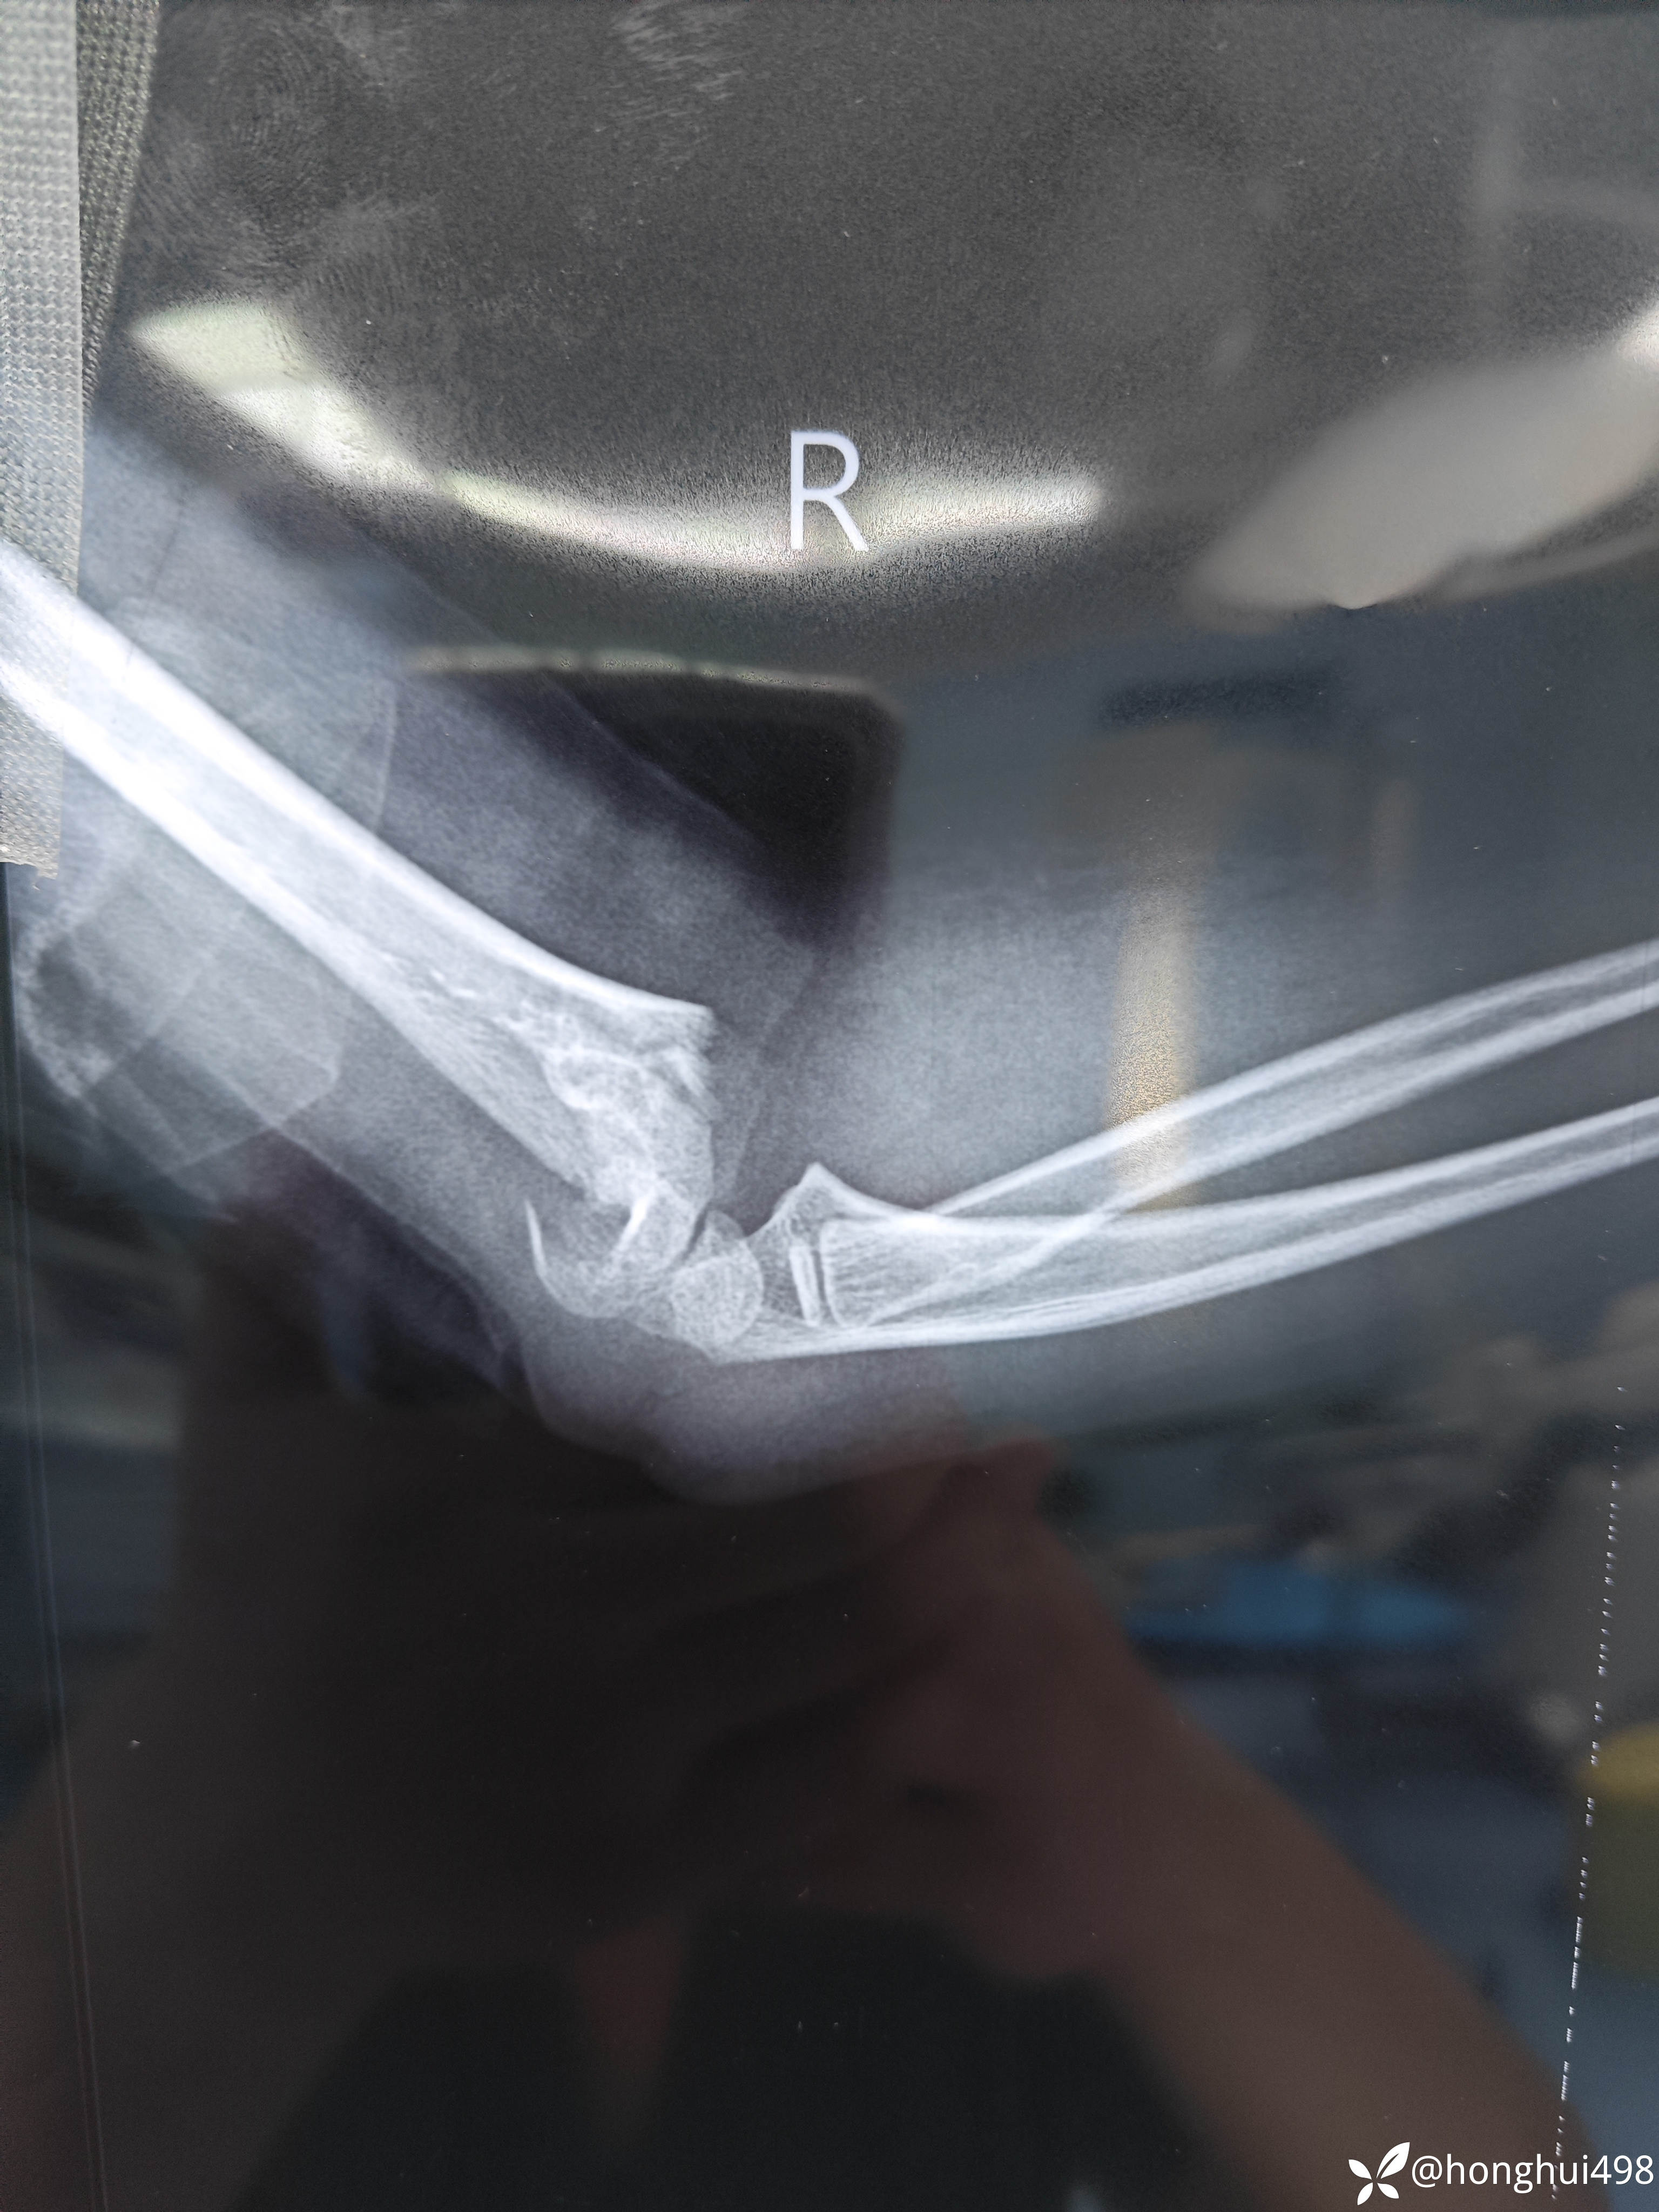

患儿女性,6岁,昨晚8点在家玩耍摔倒受伤,右肱骨髁上骨折。伤后在当地予手法复位草药外敷,伤后15小时来我院就诊,住院麻醉下闭合复位克氏针内固定。